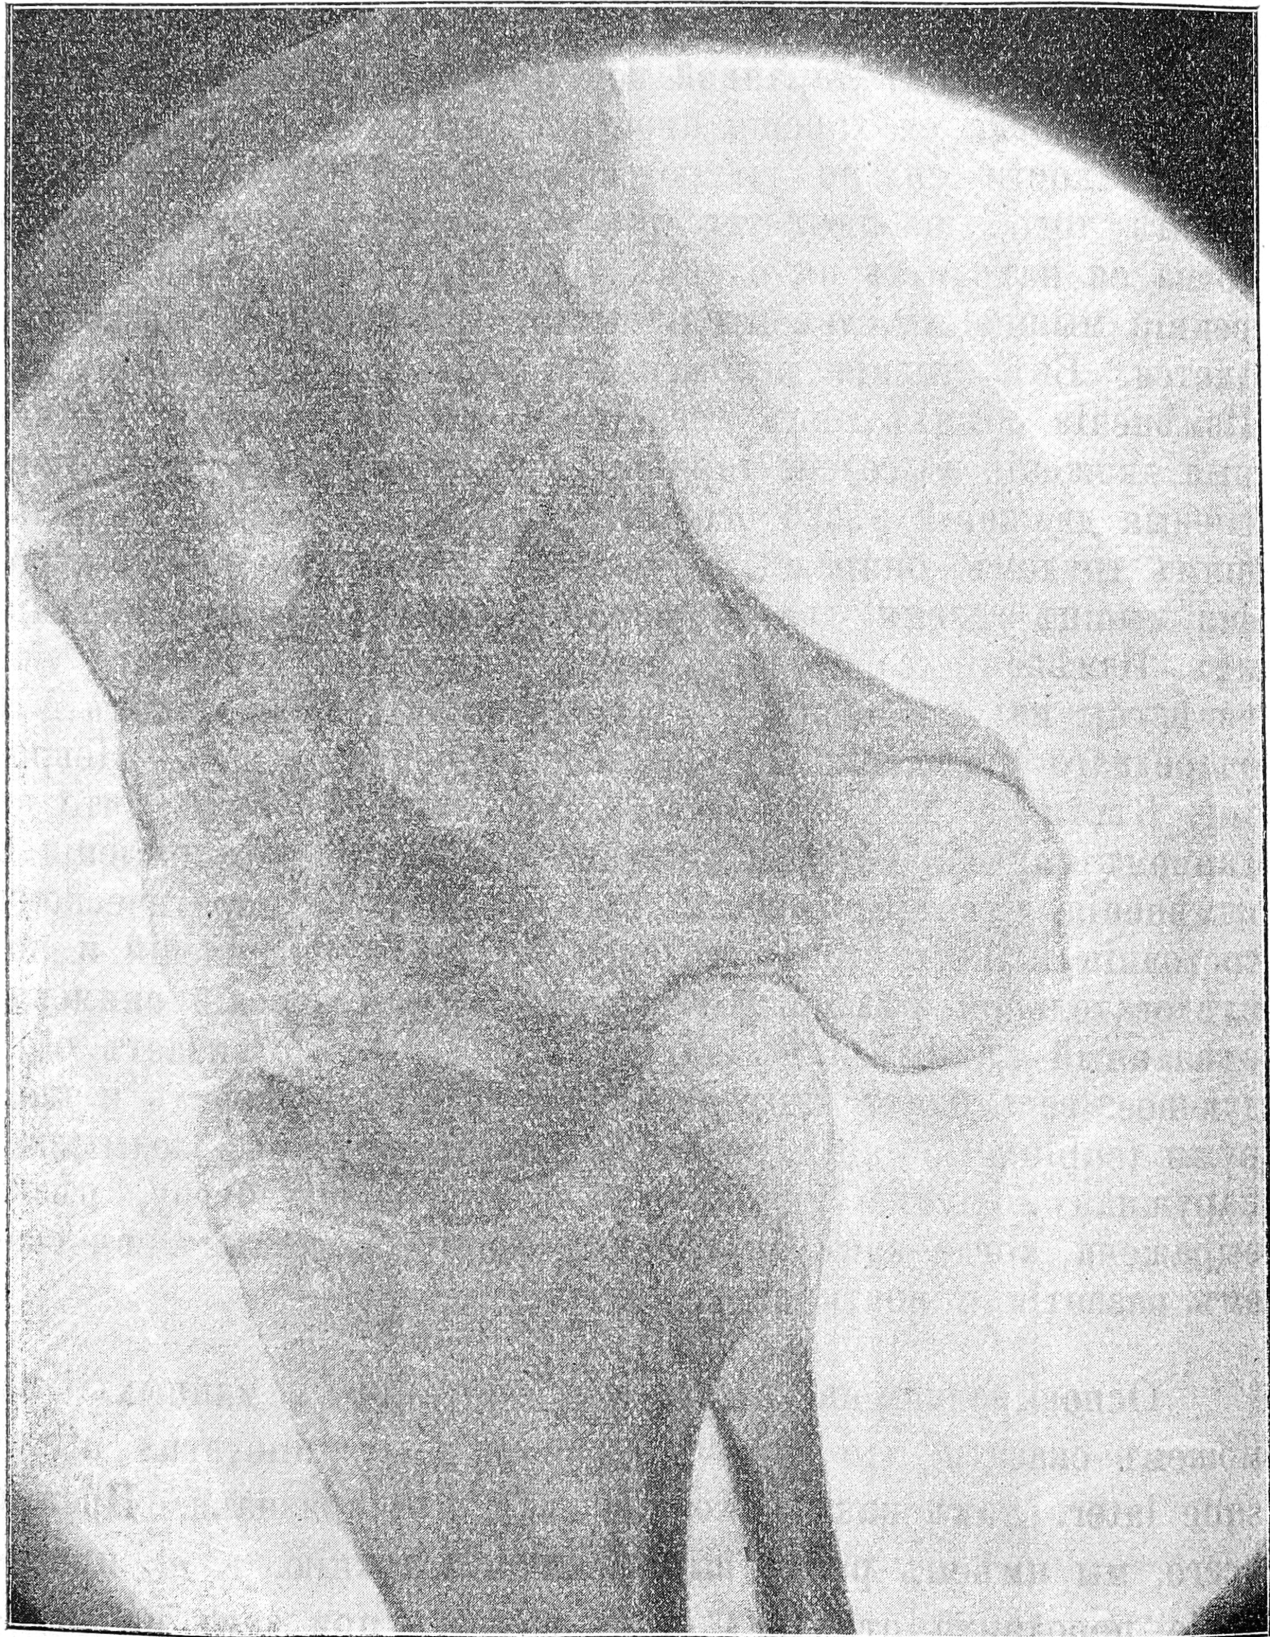

Далѣе, стопы повернуты около своей оси внутрь такъ, что подошвы (при стояніи больной) обращены всей своей поверхностью вверхъ, тылъ же стопъ всей своей наружной половиной соприкасается съ воломъ, служа плоскостью опоры при стояніи и ходьбѣ, и представляется покрытымъ мозолисто-утолщеннымъ эпидермисомъ въ области наружной части таранной, пяточной и кубовидной костей. Края стопъ изогнуты: внутренніе вогнуты и смотрятъ при стояніи впередъ и вверхъ, наружные выпуклы и расположены внизъ и назадъ. Большіе пальцы согнуты въ видѣ крючковъ и лежатъ въ одной фронтальной плоскости. Кромѣ того, стопы находятся въ сильномъ подошвенномъ сгибаніи, при чемъ замѣчается рѣзко выраженная поперечная складка на углубленной подошвѣ стопъ; тылъ же стопъ представляется очень выпуклымъ. Блокъ таранной кости смѣщенъ впередъ и кнаружи, головка ея хорошо прощупывается; кубовидная и пяточная кости сильно выдаются на наружномъ краѣ стопъ. Кромѣ того, наблюдается рѣзкое поднятіе пятки; высшая точка ея находится на одномъ уровнѣ съ мыщелками. Внутренній мыщелокъ едва прощупывается, наружный рѣзко выдается. Внѣ стоянія положеніе стопъ почти не измѣняется. Измѣненія обѣихъ стопъ представляются одинаковыми. Активныя движенія въ голено-таранномъ сочлененіи утрачены, пассивныя движенія рѣзко ограничены. Ходитъ больная съ большимъ трудомъ, опираясь на палку. Замѣчается рѣзкая атрофія мышцъ голени, доходящая почти до полнаго исчезновенія ихъ. Измѣненія со стороны нервно мышечнаго аппарата уже извѣстны изъ сообщенія д-ра Первушина (см. протоколъ VII очереднаго засѣданія Об—ва невроп. и психіатровъ, Невролог. Вѣсти. т. XVI вып. I г. 1909). Укажемъ лишь, что въ данномъ случаѣ не обнаруживается реакціи перерожденія и измѣненія чувствительности при параличѣ и паретическомъ состояніи мышцъ стопъ, голеней, кистей и предплечій и послѣдовательной рѣзкой атрофіи ихъ. Рентгеновскій снимокъ, сдѣланный съ правой ноги (см. рис. II), обнаруживаетъ слѣдующее: весь блокъ таранной кости смѣщенъ впередъ и кнаружи (subluxatio tabi), пятка находится на уровнѣ лодыжекъ, наружная лодыжка приближена къ пяточному бугру, рѣзко выражена, тогда какъ внутренняя лодыжка отстаетъ въ своемъ развитіи и почти отсутствуетъ.

Рис. II.

При выборѣ наиболѣе цѣлесообразнаго способа леченія настоящаго случая операторъ руководствовался тѣми патологоанатомическими измѣненіями, которыя наблюдались въ стопѣ. Мы имѣли 1) рѣзко выраженное приведеніе стопъ, расположенныхъ во фронтальной плоскости 2) супинапіонное положеніе искаженныхъ въ своей формѣ стопъ и 3) послѣдовательное подошвенное сгибаніе, сопровождающееся высокимъ стояніемъ пятки и приближеніемъ ея къ наружной лодыжкѣ. Патологическая анатомія внутренней косолапости, разработанная Adams´омъ, Hüter´омъ, Kocher´омъ, Bessel-Hagen’омъ и др., учитъ насъ, что наиболѣе важными факторами, вызывающими вышеописанныя измѣненія положенія и формы стопы, являются измѣненія таранной и пяточной костей. Измѣненіе таранной кости состоитъ въ подвывихѣ ея, сопровождающемся выхожденіемъ ея изъ лодыжковой ниши, а потомъ въ сильномъ выгибѣ кнутри головки и шейки tali, образующими съ осью ея тѣла довольно значительный уголъ, что обусловливаетъ, между прочимъ, рѣзкое приведеніе при косолапости. Измѣненія пяточной кости состоятъ въ выгнутости ея и въ большей высотѣ ея наружной стороны; мы останавливаемся только на существенныхъ измѣненіяхъ, обходя детали. Со стороны мягкихъ частей наблюдается укороченіе икроножной мышцы и связочнаго аппарата внутренней стороны голено-стопнаго сочлененія. Такимъ образомъ на основаніи изложенныхъ выше патолого-анатомическихъ измѣненій съ очевидностью слѣдуетъ, что оперативное исправленіе разбираемаго страданія должно быть направлено, главнымъ образомъ, на вышеописанныя части стопы. Въ видѣ добавочныхъ измѣненій могутъ наблюдаться подвывихъ ладьевидной кости, а также усиленное разростаніе кубовидной кости, вызывающей чрезмѣрное удлиненіе наружнаго края стопы. Можетъ наблюдаться и сморщиваніе подошвеннаго апоневроза. Поэтому приходится иногда усложнять оперативное пособіе.